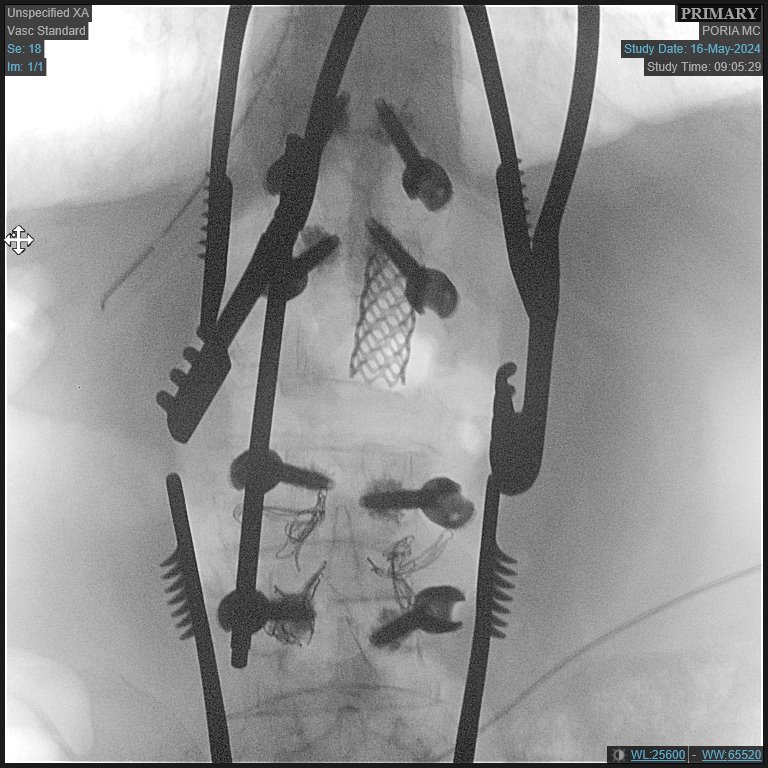

أجريت في المركز الطبي " تسفون" - " مستشفى بوريا "، في الشهر الأخير وللمرة الأولى، عملية جراحية لاستئصال غضروف من العمود الفقري من خلال عملية جراحية تجرى في منطقة الظهر للمتعالج.

وقالت متحدثة بلسان المستشفى " انه من النادر ما يتم إجراء هذه العملية الجراحية في إسرائيل، لأنه فقط في حالات استثنائية يتطلب هذا النطاق الملحوظ من الاستئصال الجراحي. ويُجرى هذا النوع من العمليات الجراحية في عدد محدود من المستشفيات في البلاد، حيث تم إجراؤها بنجاح من قبل الدكتور ليئور ماروم، مدير وحدة جراحة العمود الفقري في المركز الطبي ( تسفون )".

وقال الدكتور ليئور ماروم فيما يتعلق بهذه الحالة: "بعد إجراء التصوير الاشعاعي، رأينا أن الفقرة L2 الموجودة في الجزء السفلي من العمود الفقري، تآكلت بسبب التلوثات، مما أدى إلى تشكيل الضغط على الجهاز العصبي، مما يعتبر حالة نادرة إلى حد ما. وبعد التشاور مع المريض وعائلته، تقرر إجراء العملية الجراحية من خلال فتحة بالظهر، بدلاً من إجراء عملية فتح البطن كما متبع. وعلى الرغم من أن مثل هذه العملية تتطلب مهارة أكبر بكثير، إلا ان مخاطرها اقل على المريض وعملية التعافي منها تكون أسهل.

وخضع المريض، الذي يعاني من مشاكل طبية أخرى، للعملية الجراحية المذكورة بمساعدة فريق كبير يضم أطباء تخدير مهرة، الامر الذي مكّن من إجرائها رغم حالته الصحية المعقّدة. وقد تم خلال الجراحة إدخال طرف اصطناعي داعم (دعامة) في مكان الفقرة التي تم استئصالها - بين الحبل الشوكي والأعصاب. بالإضافة إلى ذلك تم إدخال ثمانية براغي مع مادة لاصقة لضمان عدم خروجهم من مكانهم بسبب مشاكل هشاشة العظام والتآكل وتقلص العظم. وبعد العملية استعاد المريض عافيته وعاد إلى تحريك رجليه.

وقال الدكتور ماروم عن هذه الجراحة النادرة: "يتم إجراء هذا النوع من الجراحة عادةً لمرضى الأورام السرطانية الذين يحتاجون إلى الاستئصال، أو المرضى المصابين بالتلوث مثل المريض المذكور، ولكن هذه حالة نادرة إلى حد ما. أنا سعيد أنه يمكننا الآن إجراء الجراحة للمرضى في المركز الطبي تسفون. تتطلب الحالة الطبية المعقدة للمريض مستوى عالٍ جدًا من المهارة من قبل أطباء التخدير وطاقم التمريض في غرفة العمليات خلال اجراء العملية، وأنا سعيد بوجود كوادر طبية ماهرة تمكننا من إجراء عمليات جراحية معقدة مثل هذه".